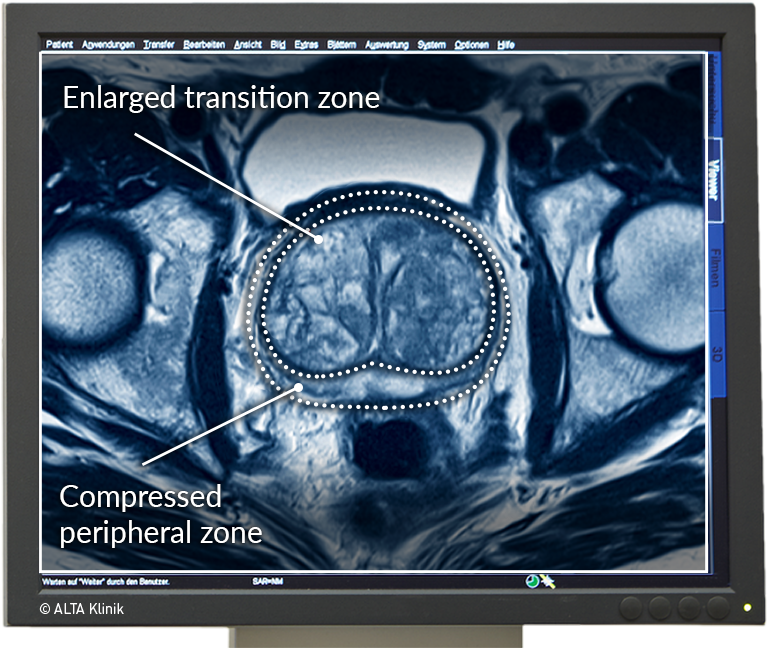

Multiparametric MRI of the Prostate – ALTA Klinik MRT อิสรภาพ ลัดเลาะกินเที่ยวร้านเด็ดใกล้สถานีรถไฟฟ้าย่านฝั่งธน | Becquetwinery

Prostata MRT – die sichere und schmerzfreie Alternative zur Biopsie MRT อิสรภาพ ลัดเลาะกินเที่ยวร้านเด็ดใกล้สถานีรถไฟฟ้าย่านฝั่งธน | Becquetwinery

Sichere Prostatavorsorge mittels MRT-Untersuchung der Prostata Erstmals Geburt im MRT aufgenommen